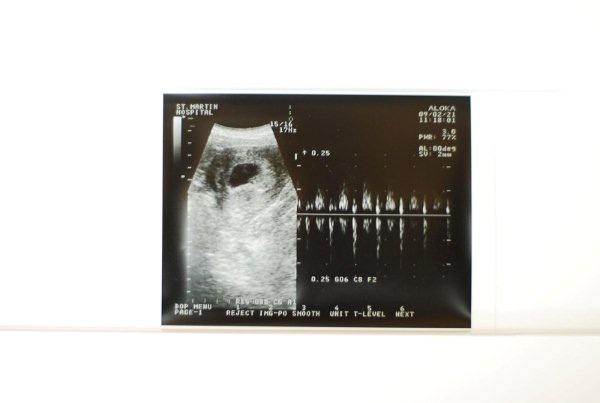

自上次4/18產檢(滿十五週)到最近一次5/16產檢(滿十九週)終於有點長進啦...